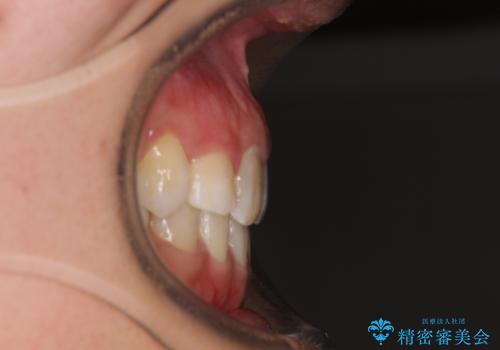

気になる八重歯 目立ちにくいハーフリンガルでの抜歯矯正

- 八重歯や前歯のデコボコを気にして来院された患者様です。

目立たない装置を希望されたので、上顎が裏側装置のハーフリンガルを選択し、上下左右の小臼歯(計4歯)を抜歯して矯正治療を行うこととしました。